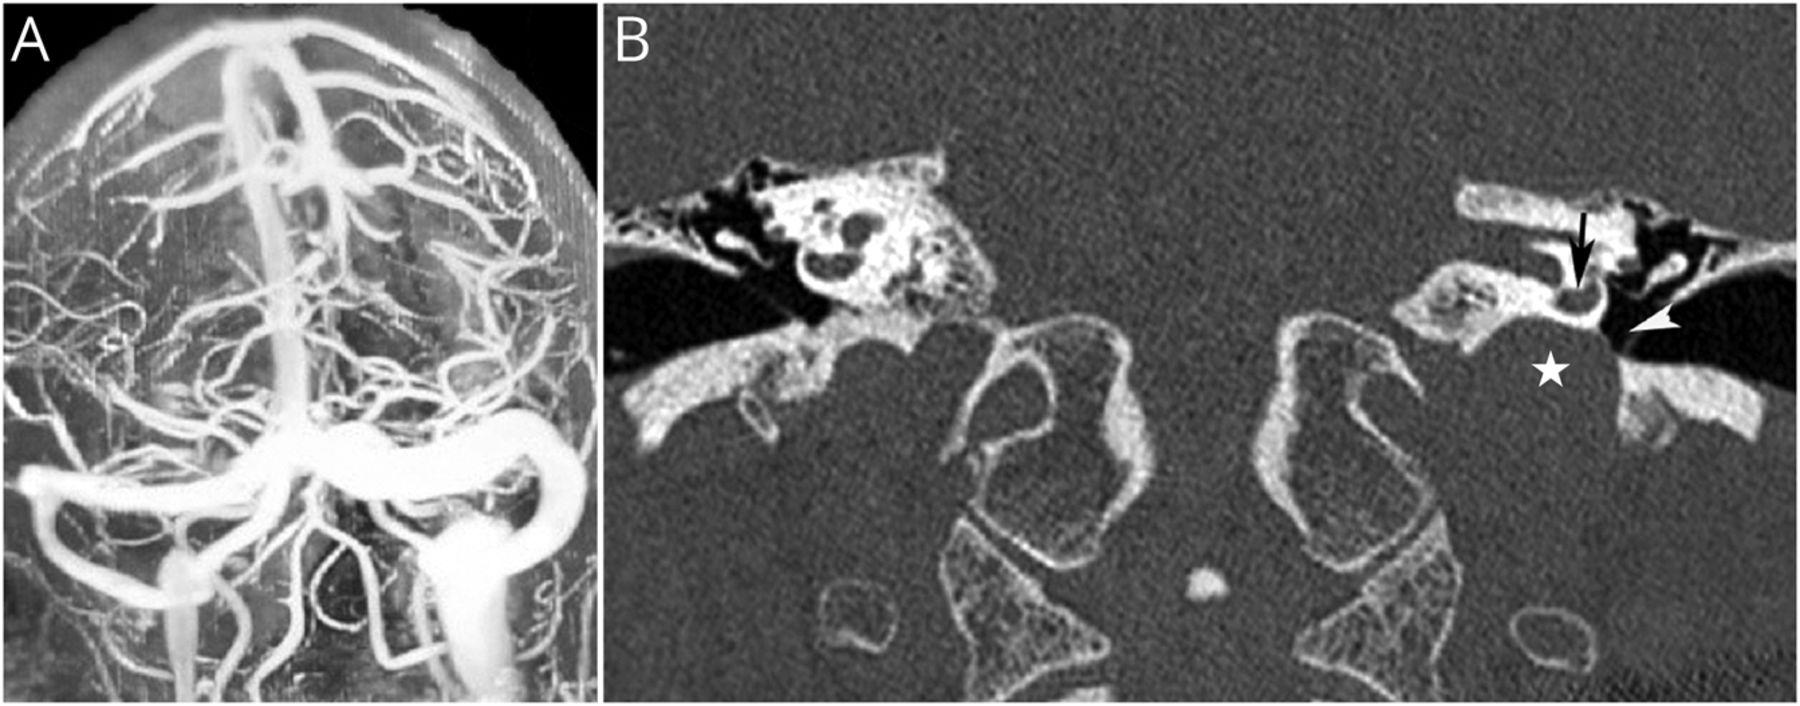

扩张左颈静脉球表明诊断为颈静脉球异常(JBA)。JBA可以是成员的颈静脉球(HRJB)或颈静脉球憩室。3HRJB被认为是当颈静脉球达到内部声学道的水平,而颈静脉球憩室是一个outpouching因扩张颈静脉球。JBA动脉瘤性扩张是一个在场的颈静脉球可能保持无症状或症状二次压力/裂开到周围的结构,包括前庭导水管、半规管,面部神经。我们的病人的历史情景左耳耳鸣和饱腹感。这一次,她看到头痛伴有急性脉动的左耳耳鸣和眩晕。确认诊断、高分辨率CT (HRCT)因为执行颞骨CT扫描是更敏感的诊断JBA内耳及其与结构的关系。HRCT显示颞骨HRJB的裂开到中耳(图)。

(一)磁共振造影术显示扩张左颈静脉球左横窦和颈内静脉与突出。(B)颞骨CT也显示扩张左颈静脉球(白色)靠近下的耳蜗(黑色箭头),张口进入左中耳(白色箭头)。